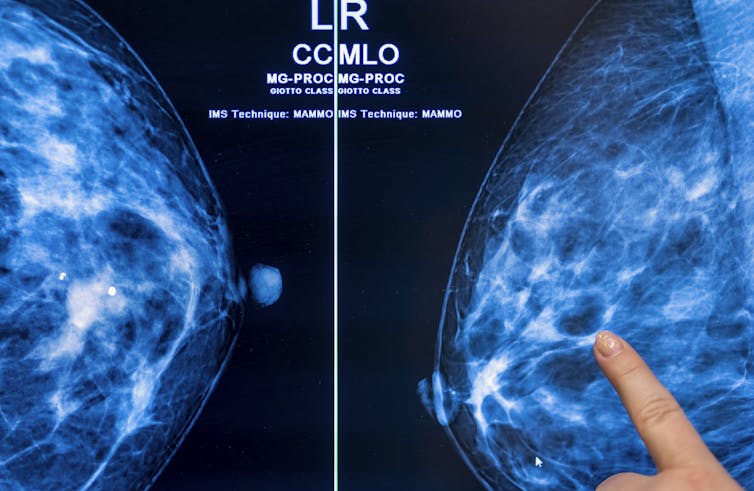

Dense breasts are composed of more fibrous, connective tissue and glandular tissue – meaning glands that produce milk and tubes that carry it to the nipple – than fatty tissue. Because fibroglandular tissue and breast masses both look white on mammographic images, greater breast density makes it more difficult to detect cancer. Nearly half of all American women are categorized as having dense breasts.

Standard mammograms use X-rays to produce two-dimensional images of the breast. A newer type of mammography imaging called tomosynthesis produces 3D images, which find more cancers among women with dense breasts. So, researchers and doctors generally agree that women with dense breasts should undergo tomosynthesis screening when available.